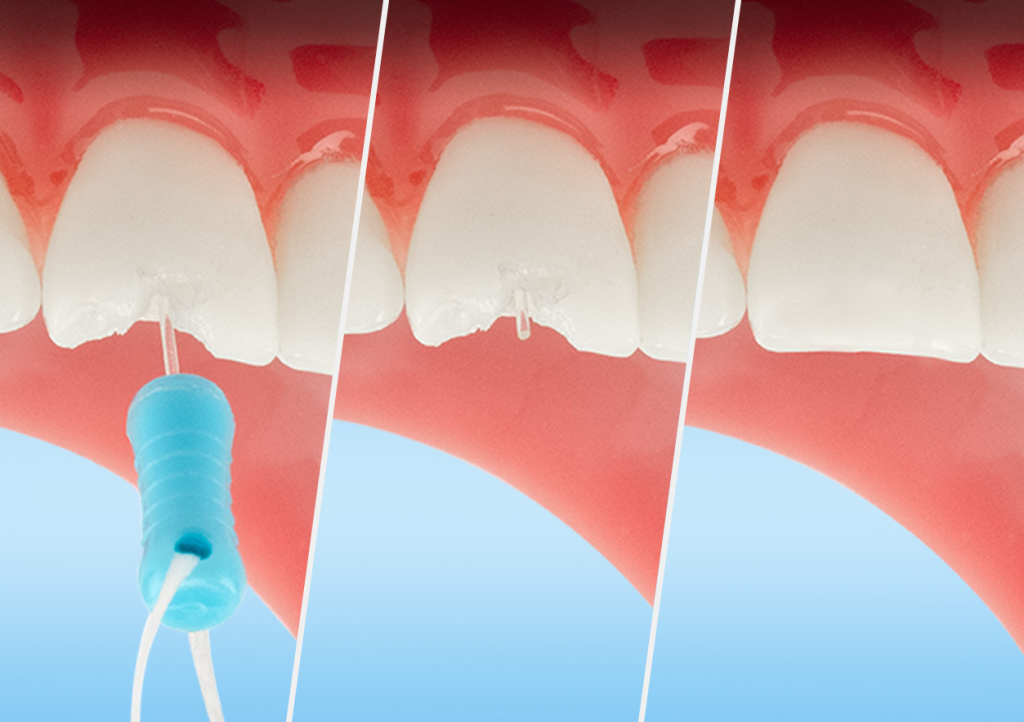

05

Pin Placement

The tooth is now ready for restoration with any composite system. The pin improves light-curing depth and shear strength.